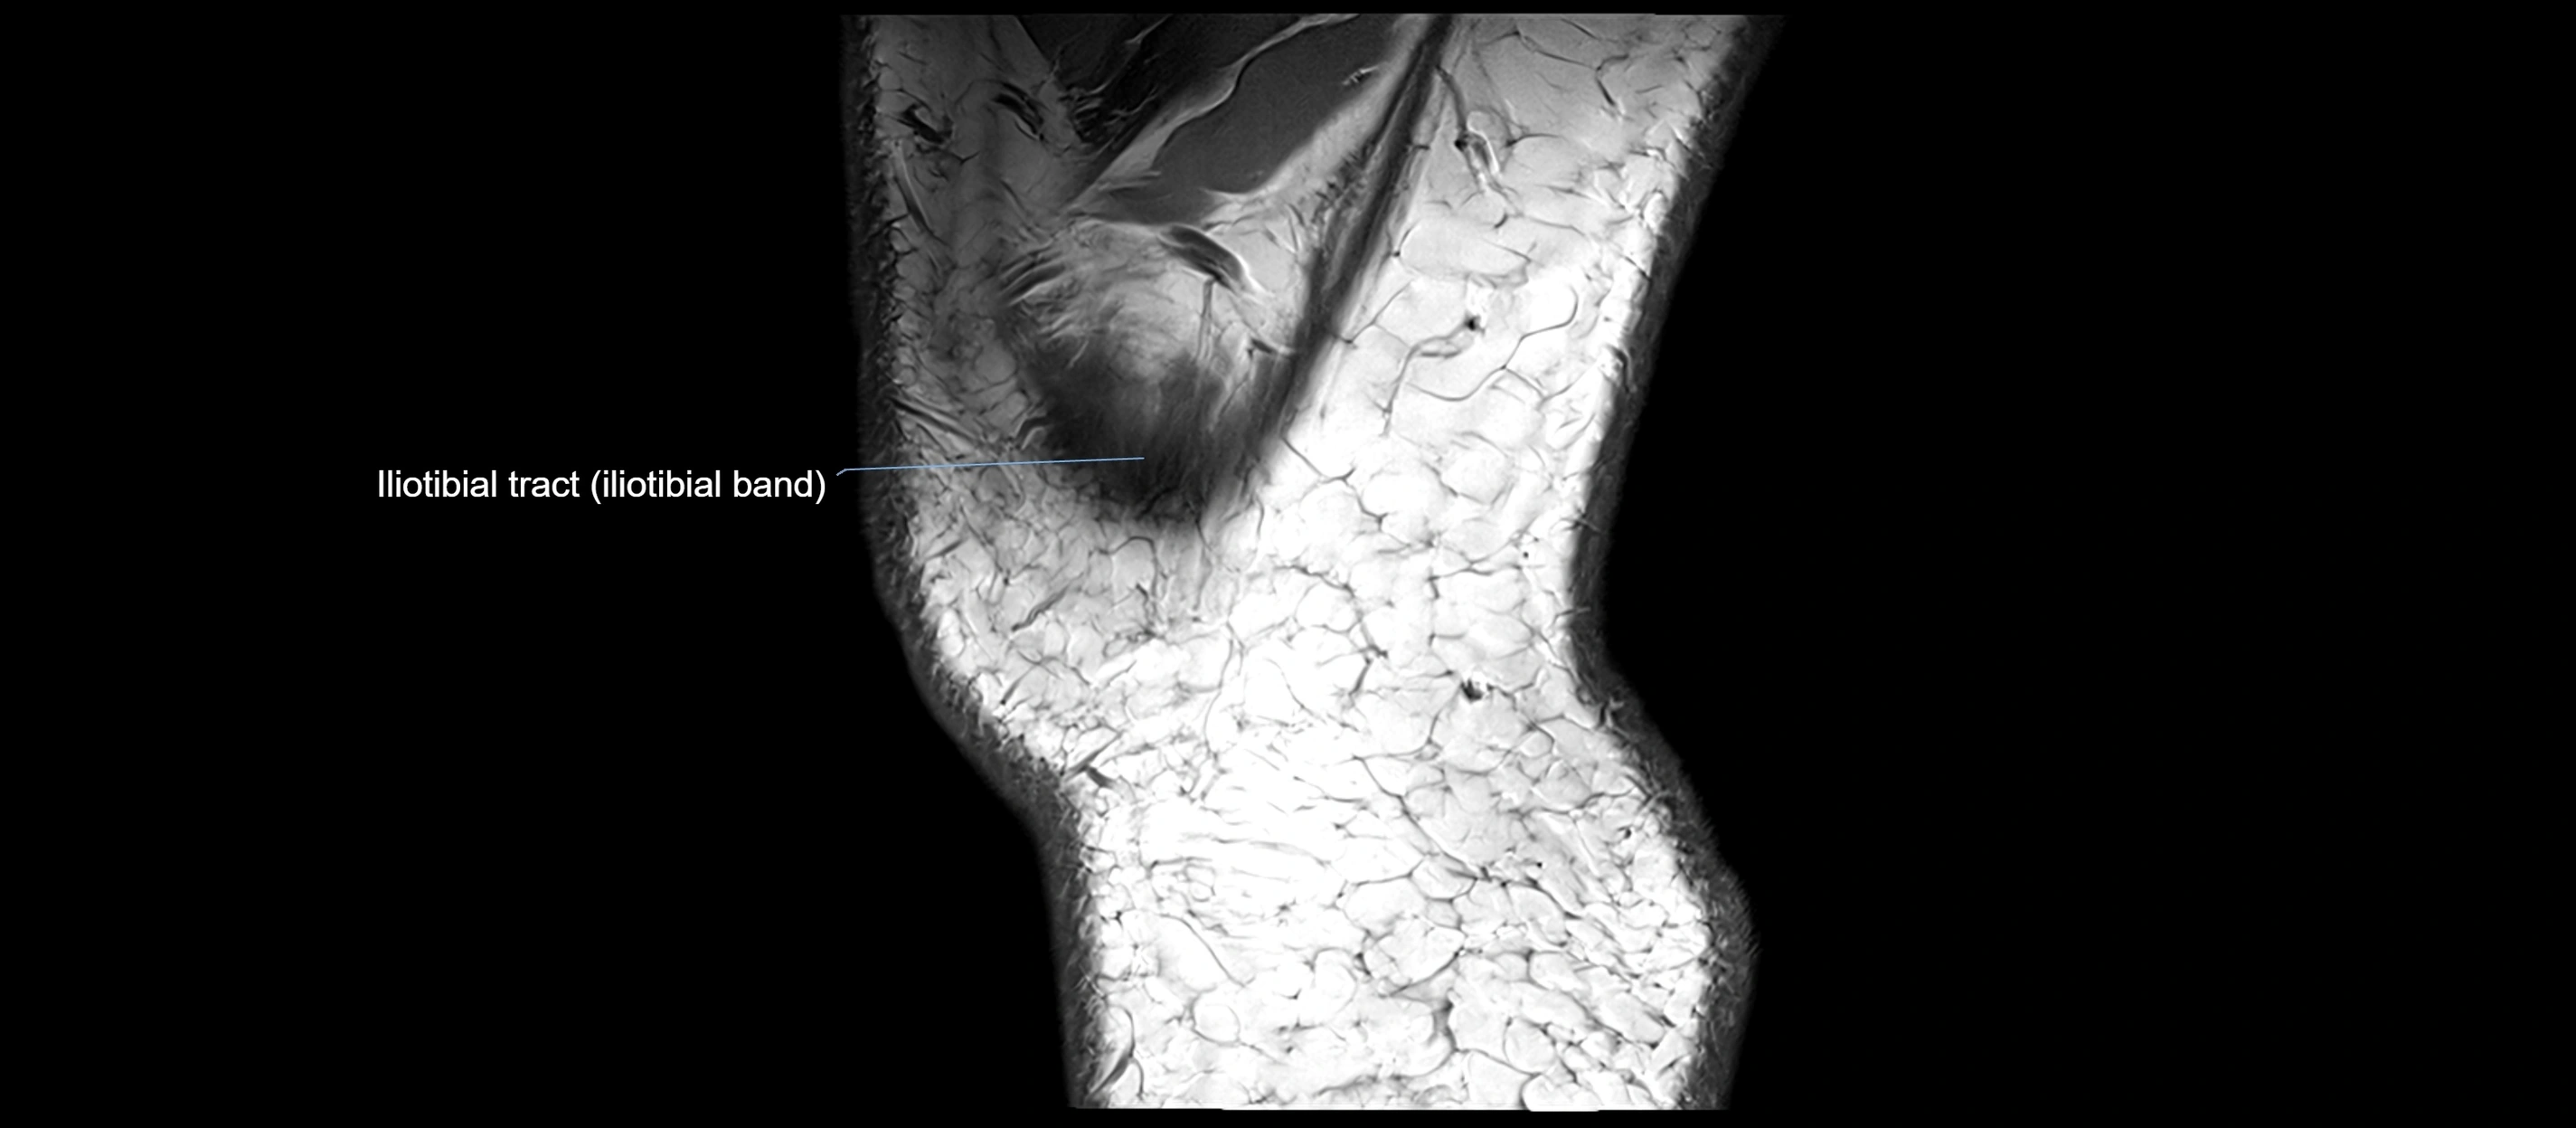

MRI images

image